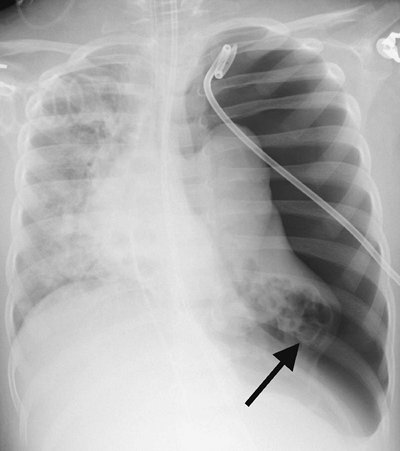

A large tension pneumothorax can be a life-threatening situation requiring rapid decompression. Radiologic signs of tension pneumothorax include contralateral displacement of the mediastinum, inferior displacement of the diaphragm, hyperlucent hemithorax, and ipsilateral collapse of the lung (Fig. 9-25).